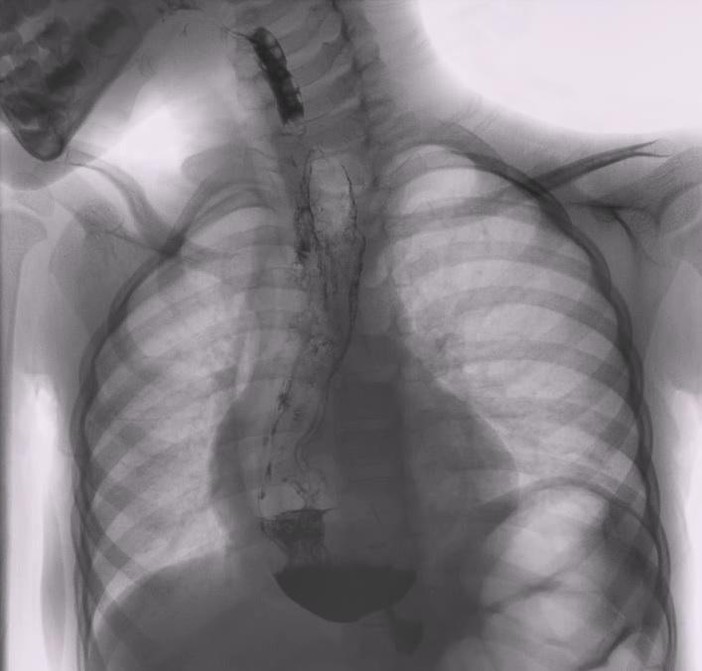

Il programma scientifico affronterà in modo multidisciplinare i principali temi legati alle malattie dell’esofago, dalle forme benigne alle patologie maligne. Nelle due giornate sono previste sessioni dedicate ai disturbi funzionali, malattia da reflusso gastro-esofageo, tumori dell’esofago e del cardias, con un focus dedicato ai nuovi trattamenti endoscopici e chirurgici, gestione perioperatoria, nutrizione clinica, nuove tecnologie comprendenti la robotica, l’intelligenza artificiale e l’ingegneria tissutale.

Tra i temi di maggiore attualità figurano anche le prospettive future delle terapie sistemiche nel carcinoma dell’esofago, il ruolo della sorveglianza attiva dopo terapia neoadiuvante, la chirurgia mini-invasiva laparoscopica e robot-assistita e l’impiego dell’intelligenza artificiale nella diagnosi e nel trattamento delle patologie esofagee.